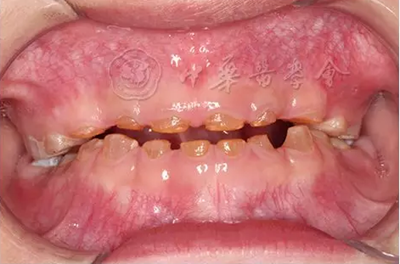

(1)疾病定義及口腔表現(xiàn):是一種罕見的以顱骨和鎖骨發(fā)育不良為主要特征的先天性骨骼系統(tǒng)發(fā)育異常綜合征,又稱Marie-Sainton綜合征,多為常染色體顯性遺傳?;颊呖杀憩F(xiàn)鎖骨單側或雙側缺如,顱骨短大,囟門和顱縫寬、延遲閉合或不閉合,面骨較小,眼距寬,鼻梁塌陷。口腔表現(xiàn)為腭蓋高拱,部分患者表現(xiàn)為腭裂或腭黏膜下裂。乳牙萌出正常,除第一恒磨牙和其他個別牙外,多數(shù)恒牙不能正常萌出,影像學檢查可見牙胚發(fā)育遲緩,乳牙根吸收遲緩,頜骨內(nèi)埋伏多顆額外牙(圖3)。有些癥狀較輕的患者可只表現(xiàn)為牙齒發(fā)育異常。

圖3 10歲顱骨鎖骨發(fā)育不全患兒曲面體層X線片,可見頜骨內(nèi)多顆埋伏額外牙,恒牙胚發(fā)育遲緩,恒牙萌出障礙